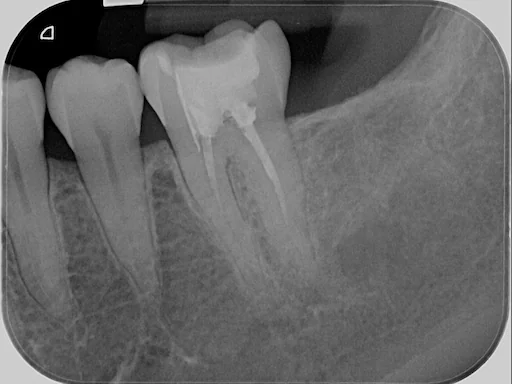

Patientenfall 36, 37 - Röntgenaufnahme der Ausgangssituation

Schritt 1

Bei diesem Patienten stellte sich der Zahn 36 aufgrund einer Längsfraktur als nicht erhaltungswürdig heraus. Zusätzlich fehlte der Zahn 37, der auf Wunsch des Patienten in eine Implantatplanung einbezogen wurde.